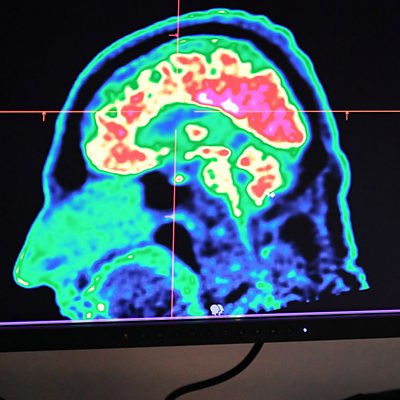

It is difficult to study the earliest stages of Parkinson's disease because people are not aware they have it, but there is one very special group of people who might hold the key. They live in villages of the northern Peloponnese in Greece and near Naples in Italy, and have a very rare genetic mutation which means that they will almost certainly develop the disease. For years professor of neurology Marios Politis, who is also director of the Neurodegeneration Imaging Group at King’s College London, had wanted to study this tiny group or people. Many of them had never been abroad before, so persuading them and organising a trip to London for them was not an easy task. But in the end 14 of them made the journey, and thanks to their generosity, Professor Politis’ team were able to make an extraordinary discovery. For decades dopamine has been considered to be the main brain chemical affected when someone has Parkinson’s disease. The team’s new research challenges this view of Parkinson’s and backed up what they had suspected for a while; that the brain chemical serotonin is heavily implicated in the early stages of the disease. The work has just been published in the journal Lancet Neurology. The Chinese authorities say the practice of taking organs from executed prisoners without their consent came to an end four years ago. But a former war crimes prosecutor has concluded that prisoners of conscience in China are still having organs removed for transplants; despite official denials from China. The allegations have been examined in detail by a tribunal set up by the charity End Transplant Abuse in China, or ETAC. Over the past two years Matthew Hill, the health correspondent for BBC in the South West of England, has been examining these allegations and has this exclusive report for Health Check. Very long hours at work can put you at risk of burnout, but unemployment is not good for your mental health either. But how much do you really need to work to start seeing the benefits of having a job? The answer is rather less than you might think. Daiga Kamerade-Hanta, senior lecturer in sociology and criminology at the University of Salford, studied data from more than 70,000 people in the UK, and the results, which have just been published in the journal Social Science and Medicine, were quite unexpected. (Photo: A picture of a human brain taken by a positron emission tomography scanner, also called PET scan. Credit: Getty Images) Health Check was presented by Claudia Hammond with comments from Sarah Boseley. Producer: Helena Selby